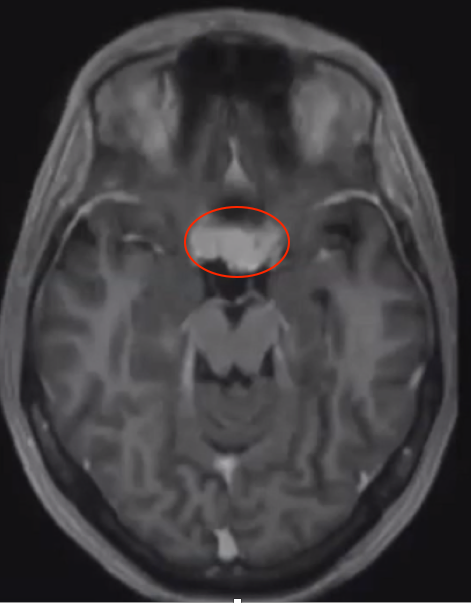

Dolenc教授指出海綿竇位于中央顱底區(qū),海綿竇腫瘤比較多的來自鞍區(qū),它會影響到Ⅲ~Ⅵ對腦神經(jīng),那么也有可能直接長到海綿竇內。腫瘤可以從各個方向蔓延入海綿竇,可以起源于鞍區(qū),也可以從周圍別處沿著顱神經(jīng)侵入海綿竇,侵入海綿竇之后在朝眼眶的地方生長。Dolenc教授著重介紹中央顱底良性腫瘤:超過鞍區(qū)的較大垂體瘤、三叉神經(jīng)鞘瘤、脊索瘤,軟骨肉瘤,軟骨瘤、血管瘤,海綿狀血管瘤、膽脂瘤、海綿竇區(qū)血栓、海綿竇腦膜瘤等。較重要的一個亞組是侵襲海綿竇的腦膜瘤。垂體瘤占本組序列的24%。這類腫瘤的特點包括因為它是從鞍區(qū)長到海綿竇,它可以沿著三組動眼神經(jīng)過來引起動眼神經(jīng)麻痹。起源于鞍區(qū)的腫瘤可以自由侵入海綿竇區(qū)域,可以沿著頸內動脈間隙和動眼神經(jīng)的間隙長過來。因該區(qū)域解剖關系復雜,腫瘤位置深,內有頸內動脈,周圍匯聚著一些重要的滑車神經(jīng)、動眼神經(jīng)和眼神經(jīng)以及上頜神經(jīng)等,而成為神經(jīng)外科手術難題。難點在于如何把腫瘤去掉,如何把后床突腫瘤挖出來。

下圖是一個病例手術前后的對照。術后腫瘤切的很干凈。